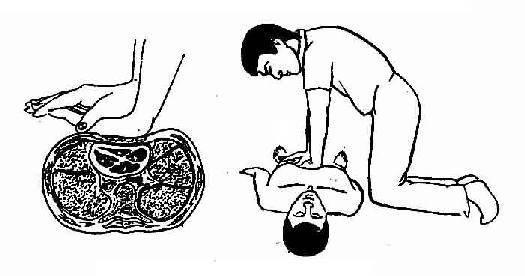

4.按压方法

(1)成人 术者双肘伸直,借身体和上臂的力量,向脊柱方向按压,使胸廓下陷3.5~5cm,尔后迅即放松,解除压力,让胸廓自行复位,使心脏舒张,如此有节奏地反复进行。按压与放松的时间大致相等,放松时掌根部不得离开按压部位,以防位置移动,但放松应充分,以利血液回流。按压频率80-100次/分。

胸外心脏按压的手法与姿势

(2)小儿 使患儿仰卧于诊疗桌上,足部略抬高以增加回心血量。术者以一手掌根部置于患儿胸骨中下部垂直向脊柱方向施力,使胸廓下陷;如是婴儿,则用一手托住患儿背部,另一手以食、中指进行按压。按压频率,年长儿80次/分,婴幼儿及新生儿100次/分。